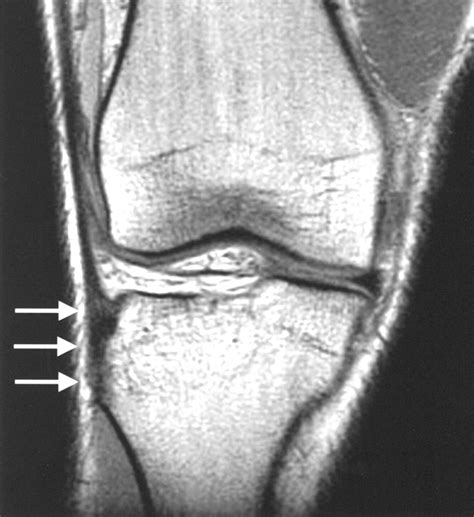

Diagnosing an IT Band Tear

Diagnosing an IT band tear typically involves a combination of physical examination and imaging tests. A healthcare provider will:

• Assess the affected area for pain, swelling, and tenderness.

• Evaluate the range of motion and strength of the knee and hip.

• Perform specific tests, such as the Noble compression test, to confirm the diagnosis.

• Order imaging tests, such as X-rays, MRI, or ultrasound, to visualize the extent of the injury.